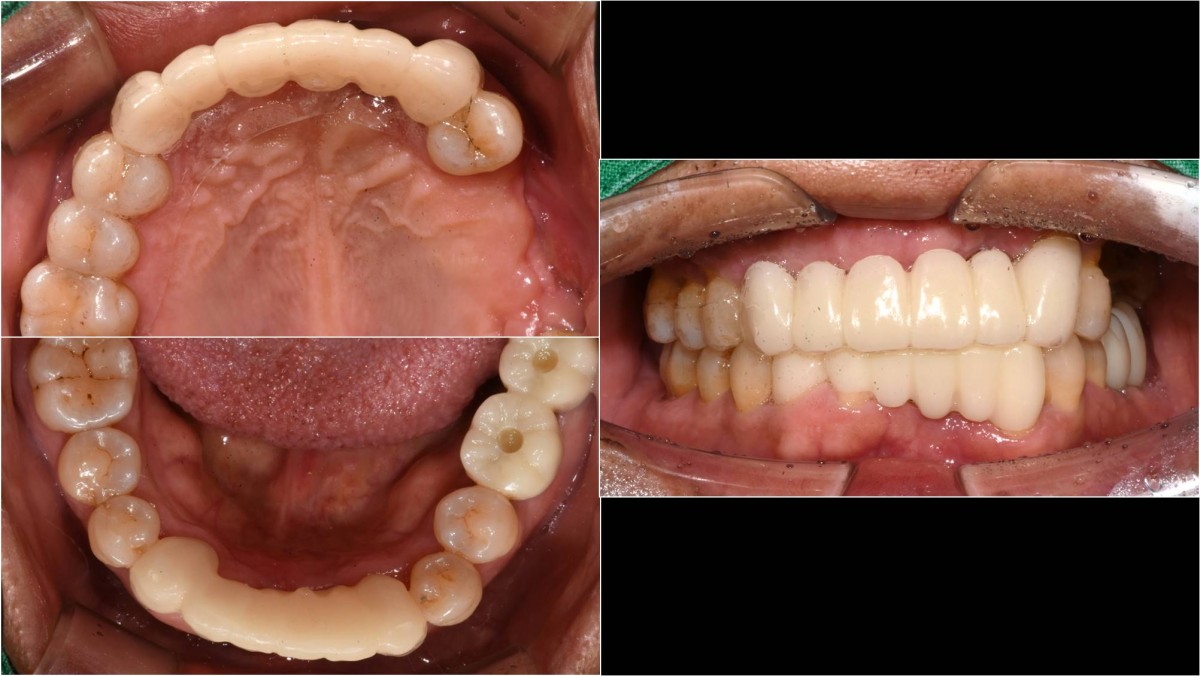

In the anterior maxilla, implant-supported fixed partial denture.

<GCpbc> A 58-year-old male is a patient undergoing implant installation in various parts. The old Br of the anterior maxilla has fallen

off and it is no longer possible to maintain it even temporarily, so a

treatment plan for the anterior teeth was made.